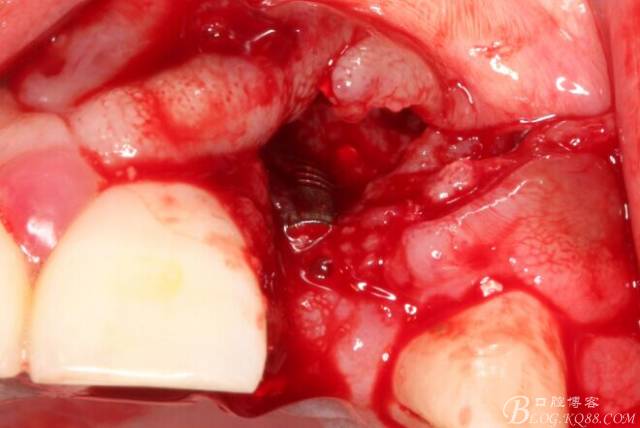

于是我果斷告知患者,手術(shù)失敗了,不能拖延,如不及時(shí)處理,炎癥繼續(xù)發(fā)展會(huì)很快波及鄰牙牙槽骨?;颊呓邮芪业慕ㄗh。切開(kāi)翻瓣,骨粉及生物膜消失了,骨吸收嚴(yán)重,幸運(yùn)的是,因?yàn)樘幚砑皶r(shí),鄰牙骨支持依然存在。

徹底掻刮。

有老師問(wèn)我,為什么不在此時(shí)同期植骨同期植入植體?我的觀點(diǎn)是:不要一次做太多事情,做得越多風(fēng)險(xiǎn)越高。再說(shuō),此時(shí)軟組織不健康,沒(méi)有健康的軟組織如何能保證GBR的成功?所以,我僅放了一塊膠原蛋白就縫上了。